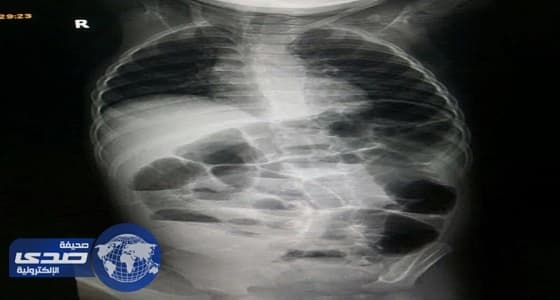

استطاع فريق طبي بمستشفى عفيف إعادة ترميم أمعاء طفل تهتكت بعد سقوط جهاز تلفاز عليه أدى لانفجار الاثني عشر والأمعاء عنده.

وكان الطفل يعاني من إصابة بليغة في منطقة البطن نتيجة تعرضه للحادثة، وعلى الفور أدخله الأطباء لغرفة العمليات وخضع لعملية جراحية استكشافية، بقيادة أخصائي الجراحة العامة والمناظير الدكتور أيمن عتيبة، وتم خلال العملية إجراء تصليح وإعادة ترميم للاثني عشر وللأمعاء نتيجة تعرضهما لقطع أثناء الإصابة وتم إنقاذ حياته بفضل الله.

وأوضح أخصائي الجراحة العامة والمناظير بالمستشفى الدكتور أيمن عتيبة، أن حالات الإصابة بالاثني عشر بعد ضربات البطن غير النافذة تعد من الحالات النادرة الحدوث وتحتاج لدقة عالية لتشخيصها وإصلاحها جراحياً.